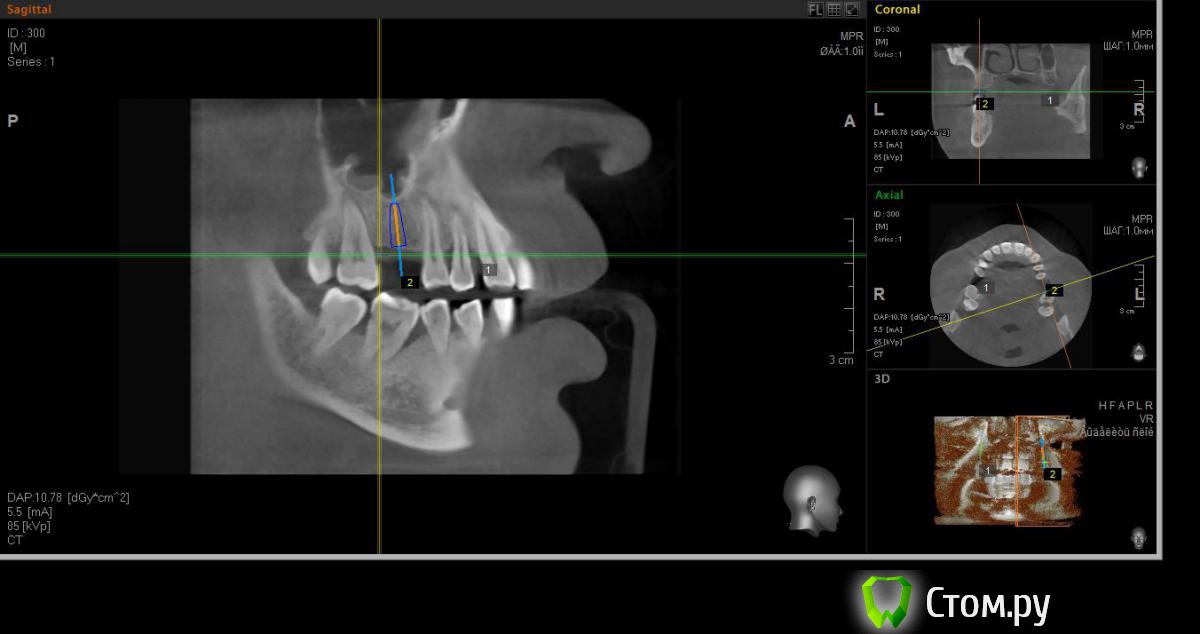

faity Опубликовано 18 мая, 2014 Автор Поделиться Опубликовано 18 мая, 2014 хочу вот так сделать, на 1.6 мягкий лифт, в обл 2.6 не лезтьвинты Ankylos 1.6- 4,5/11 2.6- 3,5/9,5кости в области 1.6- 7,5мм, должно хватить для закрытого, открытый пациент не потянет по финансам.какие мысли? Ссылка на комментарий

red_butler Опубликовано 19 мая, 2014 Поделиться Опубликовано 19 мая, 2014 Я бы не планировал хирургию исходя из финансовых пожеланий пациента, и 1.6 вел бы с открытым синусом. Представьте что при закрытом порвали мембрану, открытый придется делать, и за свой счет. Винт в позицию 1.6 поставил бы меньшего диаметра Ссылка на комментарий

faity Опубликовано 19 мая, 2014 Автор Поделиться Опубликовано 19 мая, 2014 Я бы не планировал хирургию исходя из финансовых пожеланий пациента, и 1.6 вел бы с открытым синусом. Представьте что при закрытом порвали мембрану, открытый придется делать, и за свой счет. Винт в позицию 1.6 поставил бы меньшего диаметрапоменял винты на 3,5/11 Ссылка на комментарий

red_butler Опубликовано 19 мая, 2014 Поделиться Опубликовано 19 мая, 2014 (изменено) Не знаю диаметры винтов в этой системе, между 3.5 и 4.5 Промежуточного нет?А 2.6 без синуса и диаметр больше Изменено 19 мая, 2014 пользователем red_butler Ссылка на комментарий

faity Опубликовано 19 мая, 2014 Автор Поделиться Опубликовано 19 мая, 2014 Не знаю диаметры винтов в этой системе, между 3.5 и 4.5 Промежуточного нет?А 2.6 без синуса и диаметр большепромежуточных к сожалению нета 2,6 больше не получитсяэто при ныненшнем радиусе и положении, если делать больше винт, то больше углублять, а тогда в синус провалюсь Ссылка на комментарий